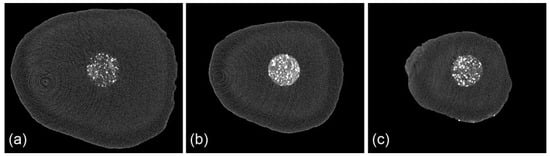

Figure 3.

Micro-CT images of the filling material in transversal plane (d ≈ 1 mm) at different levels: (a) at 3 mm (approximately) from the resected apex; (b) at 2 mm; (c) at 1 mm.